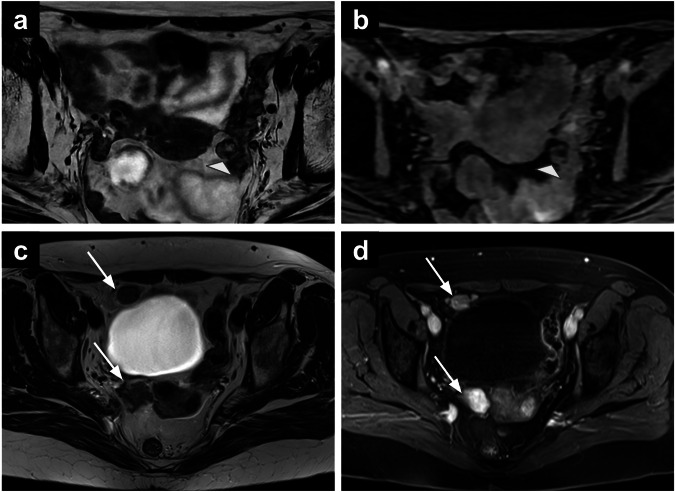

女性骨盆MRI的偶然发现给诊断带来了挑战,并可能具有重要的临床意义。定义为与主要影像学指征无关的异常,随着MRI在妇科实践中的广泛应用,这些发现变得越来越普遍。标准的妇科MRI方案,包括T1和t2加权序列,弥散加权成像和对比增强序列,促进了许多妇科外异常的特征,从良性到严重病变。这篇综述提出了一种基于区隔的方法来识别妇科外的发现,讨论他们的影像学特征和鉴别诊断。这种方法可以帮助放射科医生系统地评估偶然发现,潜在地提高对临床相关异常的认识,并支持及时的临床决策。关键相关性声明:骨盆MRI附带的妇科外发现可能会带来重大的诊断挑战。系统评估骨盆MRI附带的妇科外发现可以提高放射科医生对临床相关异常的认识。重点:骨盆MRI的妇科外偶然发现是常见的,范围从良性到恶性。基于腔室的分类——将女性骨盆分为前腔室、侧腔室、后腔室、肌肉骨骼腔室和其他腔室——为解释骨盆提供了一个系统的框架。全面评估所有MRI序列,包括大视场图像,可能有助于确定临床相关的偶然发现。

Incidental findings on female pelvic MRI present diagnostic challenges and may have significant clinical implications. Defined as abnormalities unrelated to the primary imaging indication, these findings have become increasingly prevalent with the expanded use of MRI in gynaecological practice. Standard gynaecological MRI protocols, incorporating T1- and T2-weighted sequences, diffusion-weighted imaging, and contrast-enhanced sequences, facilitate the characterisation of numerous extra-gynaecological abnormalities, ranging from benign to critical lesions. This review proposes a compartment-based approach for identifying extra-gynaecological findings, discussing their imaging characteristics and differential diagnoses. This approach may help radiologists systematically assess incidental findings, potentially improving the recognition of clinically relevant abnormalities and supporting timely clinical decision-making. CRITICAL RELEVANCE STATEMENT: Incidental extra-gynaecological findings on pelvic MRI can present significant diagnostic challenges. Systematic evaluation of incidental extra-gynaecological findings on pelvic MRI can improve radiologists' awareness of clinically relevant abnormalities. KEY POINTS: Extra-gynaecological incidental findings on pelvic MRI are common and range from benign to malignant conditions. A compartment-based classification-dividing the female pelvis into anterior, lateral, posterior, musculoskeletal, and miscellaneous compartments-provides a systematic framework for interpretation. Thorough assessment of all MRI sequences, including large field-of-view images, may help identify clinically relevant incidental findings.